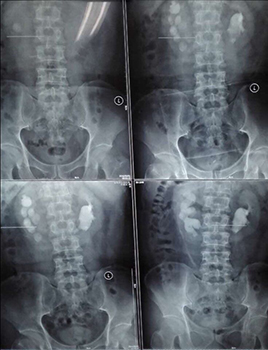

兩位患者均因腰背部疼痛來我院看診,住院后行CT等檢查確診為馬蹄腎合并腎結石,一例左腎結石大小約2.5cm,另一例右腎結石大小約3.0cm。

經(jīng)皮腎鏡取石術是泌尿外科風險最大、技術要求最高的手術之一,而馬蹄腎是一種先天性畸形,本該相對獨立的左右兩腎的上端或者下端長在一起,形似“U”形馬蹄,且腎旋轉不良,腎盞位于腎前方,輸尿管走形異常,所以馬蹄腎患者更易出現(xiàn)各種合并癥,例如泌尿系統(tǒng)結石、感染、腎積水、尿路梗阻等。這種腎畸形增加了經(jīng)皮腎鏡取石手術的定位穿刺和建立操作通道的難度,術中出血風險也更高。如果通道建立不理想,可能找不到結石,無法完成碎石取石。

馬蹄腎